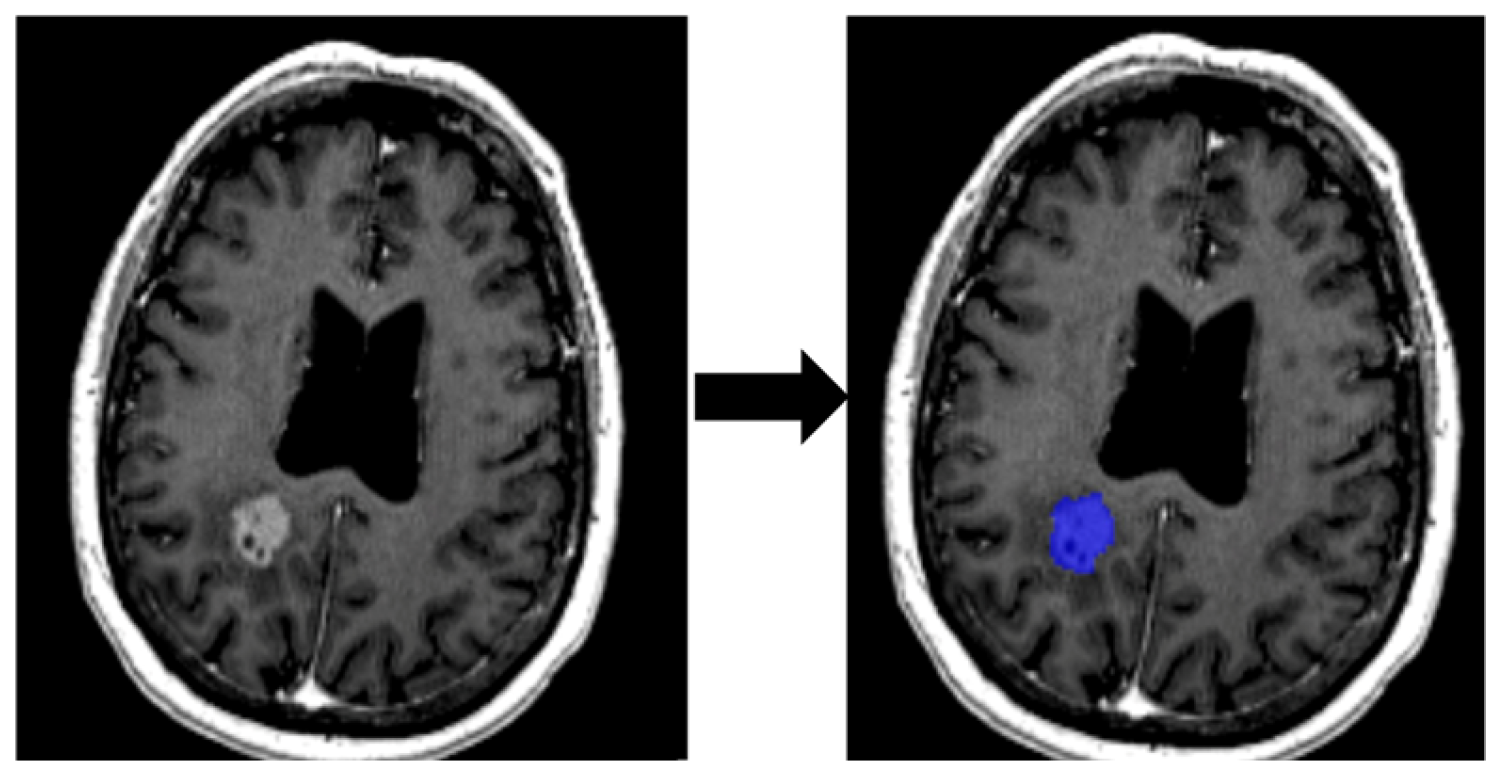

2.3.1. Segmentation of ROI

2.3.2. Feature Extraction